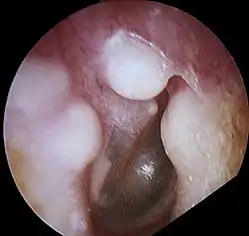

ورم عظمي

الورم العظمي (بالإنجليزية: Osteoma) هو قطعة جديدة من عظم تنمو على قطعة من عظم آخر، عادة ما تحدث على الجمجمة، وهو ورم حميد.[1] عندما ينمو الورم العظمي على عظام أخرى، يعرف ذلك باسم "الورم العظمي المثلي"؛ أما عندما ينمو على أنسجة أخرى، يسمى "ورم عظمي متغاير".

يمثل الورم العظمي أكثر أورام الأنف والجيوب المجاورة للأنف من حيث كونها حميدة. سبب الإصابة بالورم العظمي غير مؤكد، لكن النظريات المقبولة بشكلٍ عام تقترح أسباباً جنينية أو رضحية، أو معدية. كما قد يترافق الورم العظمي مع متلازمة غاردنر. قد تتسبب الأورام العظمية القحفية الأكبر حجماً بحدوث ألم في الوجه وصداع وعدوى بسبب انسداد القنوات الجبهية الأنفية. غالباً ما يظهر الورم العظمي القحفي الوجهي من خلال علامات وأعراض في العينين كجحوظ العين.[2]